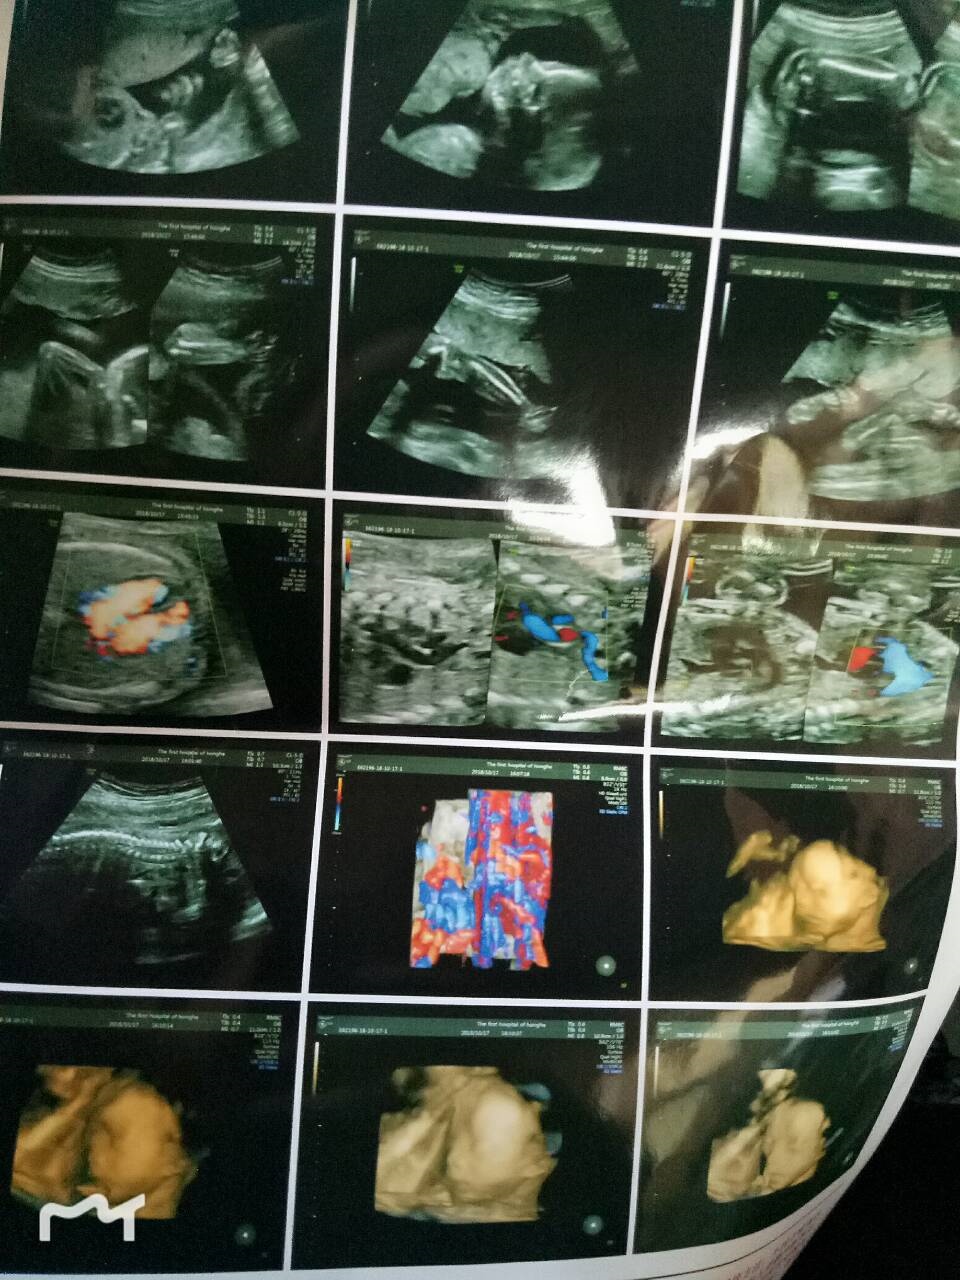

孕25周+6天

我做的也有个强光点,医生也说建议染色体检测,可是已经过了时间了,这边医院都不能做,好担心。看网上也有好多这种情况

左心室内可见强光斑,医生有跟你说什么吗,我今天才做完四维,也有这个,说是让我做无创。。。现在再挂专家号看看